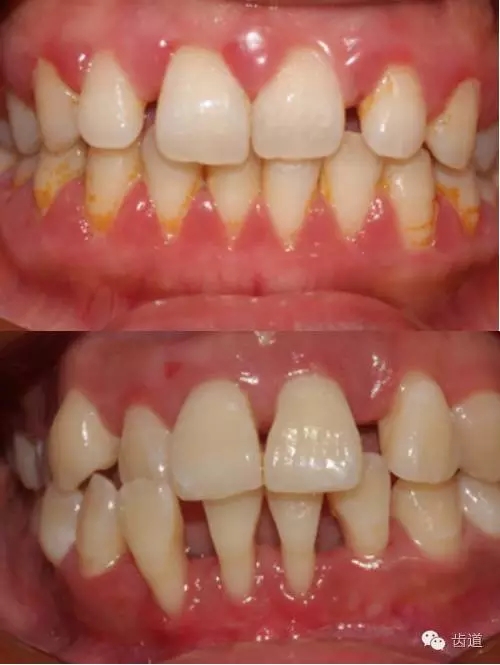

1、口腔衛(wèi)生狀況及局部刺激物(牙菌斑、牙石,不良修復(fù)體)

牙石及不良修復(fù)體